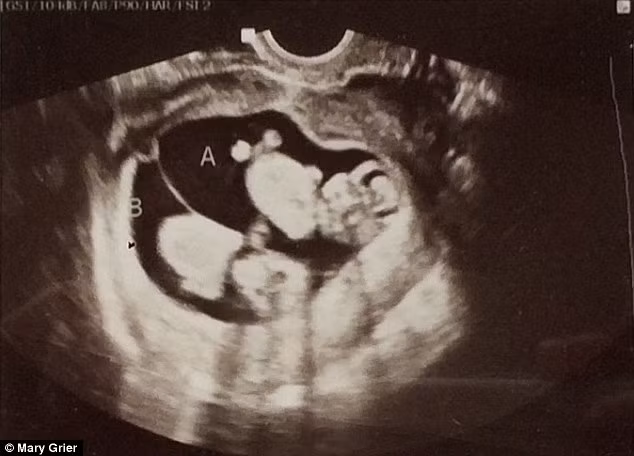

Cặp vợ chồng Mary và Brad Grier người Mỹ phát hiện con trai họ ở tuần thai thứ 20 đã bị hội chứng truyền máu song thai.

Mặc dù đã được phẫu thuật lấy thai ra ngoài ở tuần thứ 23 nhưng một trong hai em bé đã qua đời.